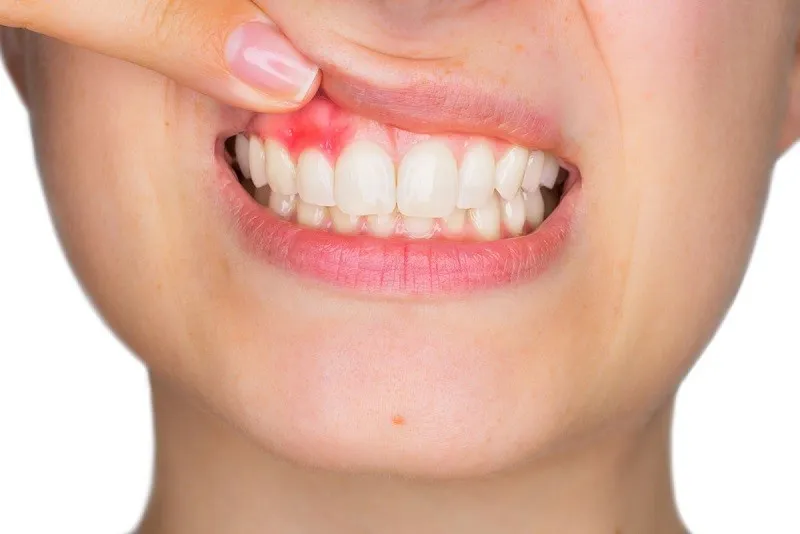

nú răng bị chảy máu là một triệu chứng phổ biến mà nhiều người gặp phải trong sinh hoạt hàng ngày, đặc biệt khi đánh răng hoặc

Sưng lợi là tình trạng phổ biến mà nhiều người gặp phải trong cuộc sống hàng ngày. Đây không chỉ gây đau nhức và khó chịu mà